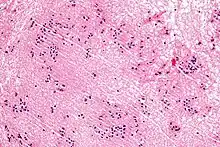

| Micrograph of a subependymoma showing the characteristic clustering of nuclei. H&E stain. | |

The diagnosis is based on tissue, e.g. a biopsy. Histologically subependymomas consistent of microcystic spaces and bland appearing cells without appreciable nuclear atypia or mitoses. The nuclei tend to form clusters.